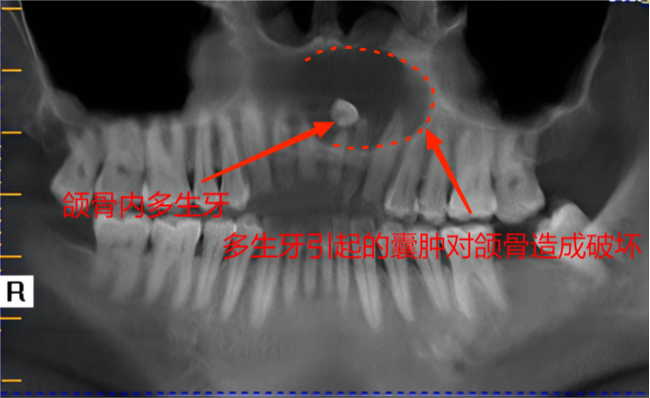

阻生于颌骨内的牙齿形成颌骨囊肿(另一病例)